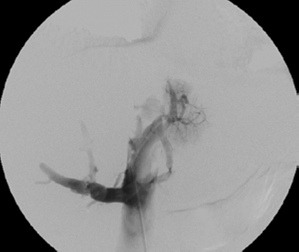

Se practicó una cavografía y se encontró trombosis de la vena cava inferior, desde la vena renal izquierda; la vena cava superior era normal (figura 3). Se procedió a cambiar el introductor femoral por un 8 French (Cordis™ - Johnson & Johnson) y se practicó una trombectomía venosa percutánea con el sistema de tromboaspiración de penumbra (Penumbra Medical Systems, Inc.), extrayendo moderada cantidad de coágulos subagudos.